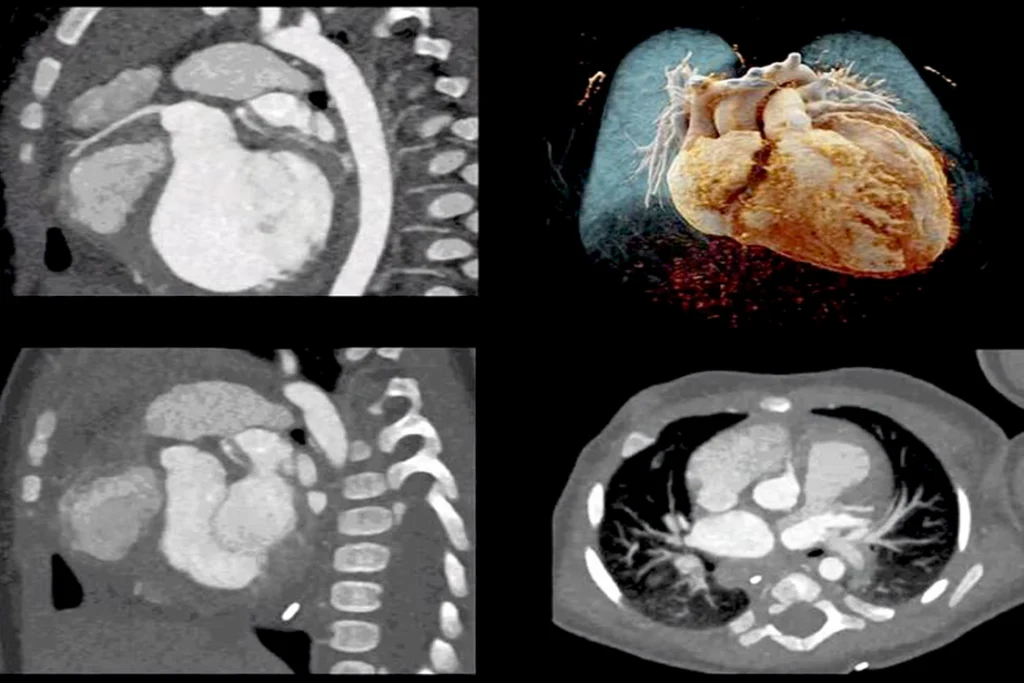

Image Acquisition and Optimization

- Delves into the technical aspects of acquiring high-quality cardiac CT images.

- Explains different scanning protocols (axial, helical, high-pitch spiral) and their applications.

- Focuses on electrocardiogram (ECG) gating and its role in minimizing motion artifacts.

- Covers prospective and retrospective ECG gating techniques and their implications.

- Explores strategies for optimizing image parameters (kVp, mAs, collimation, pitch).

- Aims to achieve optimal image resolution while adhering to the ALARA principle.

- Discusses factors affecting image quality (patient size, heart rate variability, metallic implants).

- Covers techniques to mitigate these image quality issues.

- Covers post-processing techniques: multiplanar reconstructions (MPR), maximum intensity projections (MIP), and volume rendering.

- Guides you through a systematic approach to interpreting cardiac CT images.

- Includes assessing image quality and identifying normal and abnormal findings.

- Covers quantifying coronary artery stenosis and evaluating cardiac function.